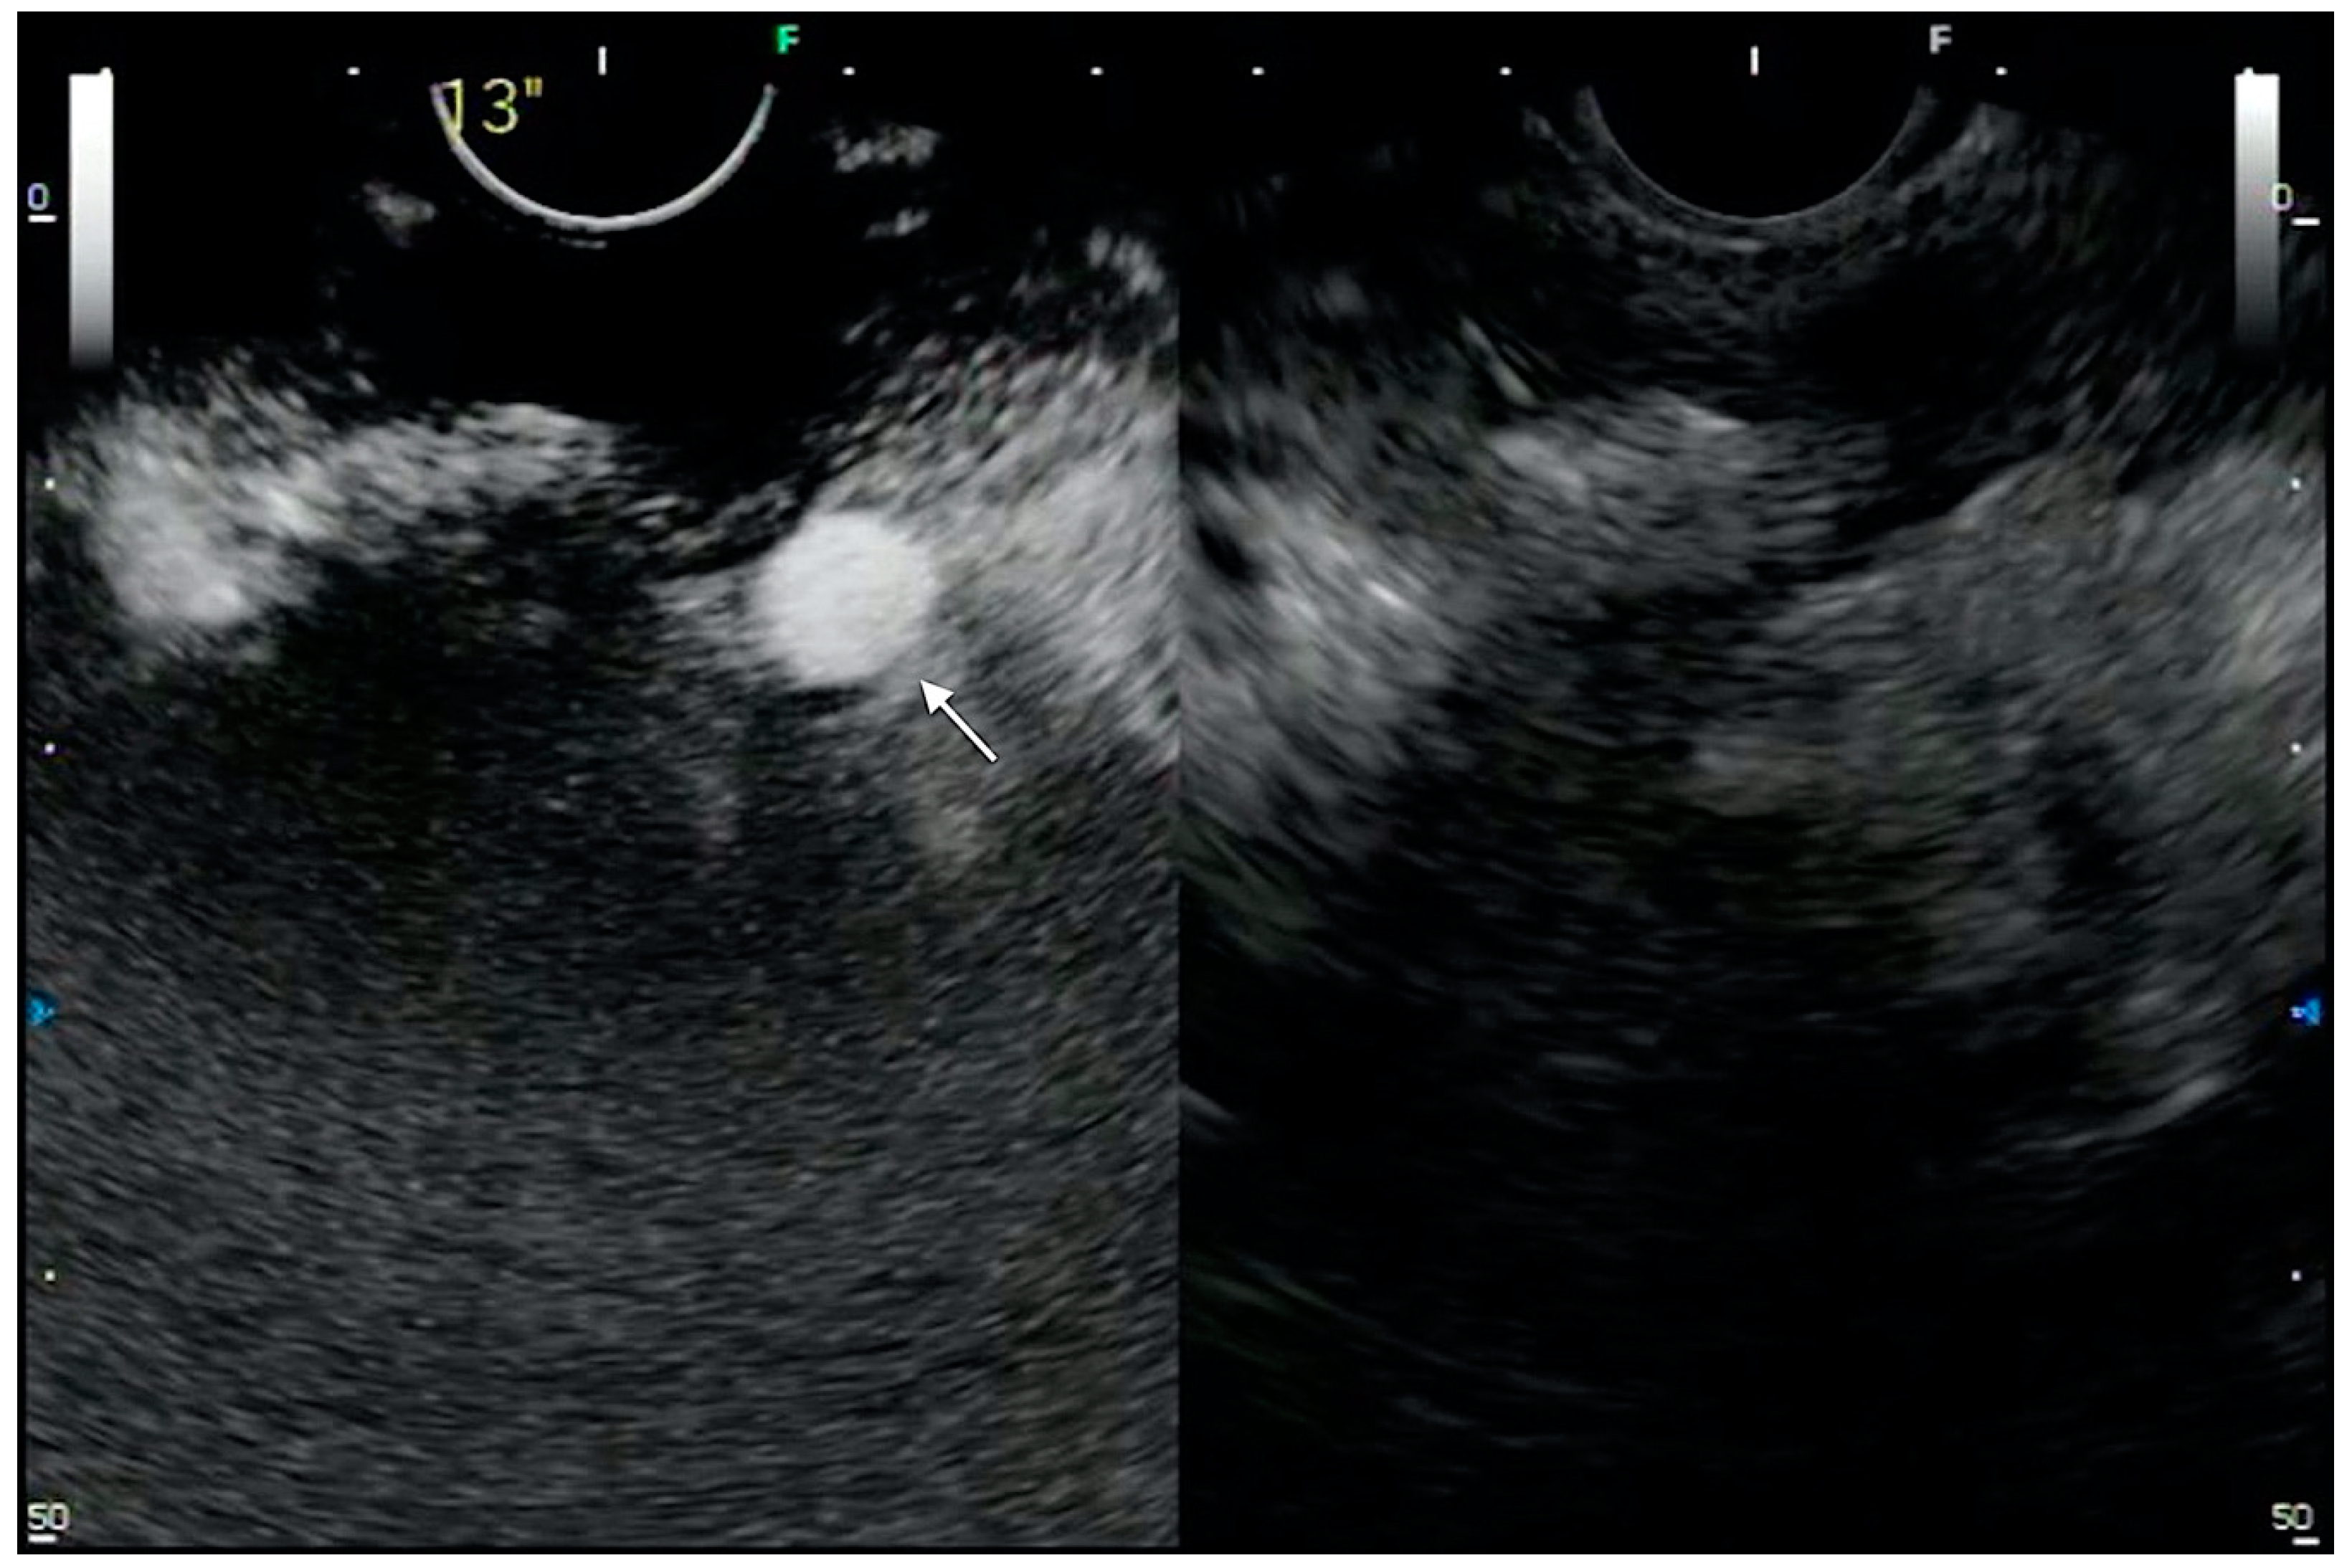

- Choi, J.-H.; Seo, D.-W.; Song, T.J.; Park, D.H.; Lee, S.S.; Lee, S.K.; Kim, M.-H. Utility of Contrast-Enhanced Harmonic Endoscopic Ultrasound for the Guidance and Monitoring of Endoscopic Radiofrequency Ablation. Gut Liver 2020, 14, 826–832. [Google Scholar] [CrossRef]